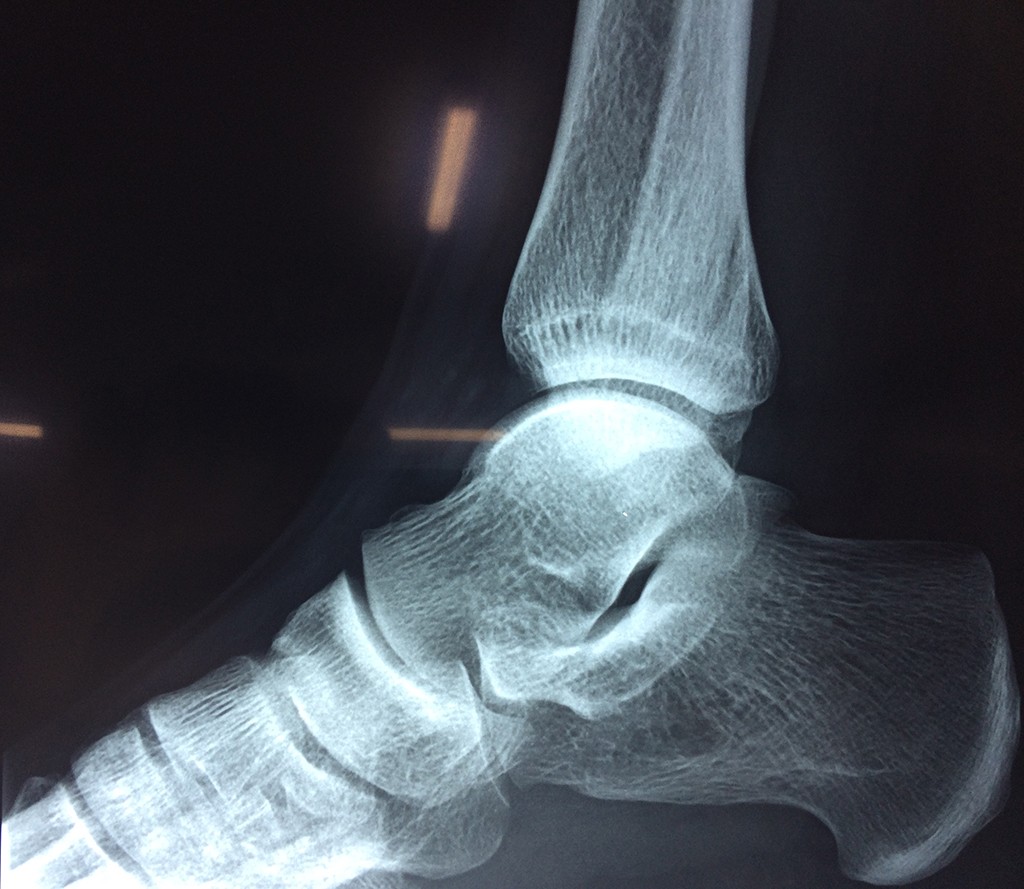

Una fractura de tobillo es la rotura de uno o más de los huesos del tobillo. Estas fracturas pueden ser:

Algunas fracturas de tobillo pueden requerir cirugía si:

- Los extremos de los huesos están desalineados entre sí (desplazados).

- La fractura se extiende hasta la articulación del tobillo (fractura intra-articular).

- Los tendones o ligamentos (tejidos que sujetan los músculos y los huesos entre sí) están rotos.